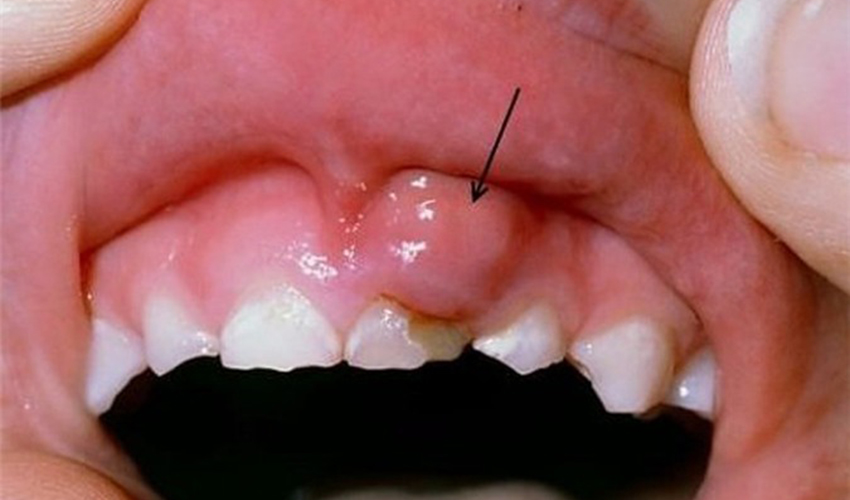

2. Xuất hiện khối u tại vùng nướu răng

Khối u ung thư sẽ phát triển nhanh sản sinh tế bào cực nhanh nên chỉ trong một thời gian ngắn, vì vậy khi quan sát thấy vùng nướu răng xuất hiện khối u, hơi đau và có màu đậm hơn vùng nướu thì bạn nên cảnh giác vì đây có thể là khối u, để biết là khối u lành tính hay ác tính thì bạn cần tới bệnh viện khám sinh thiết phát hiện chính xác nhất.